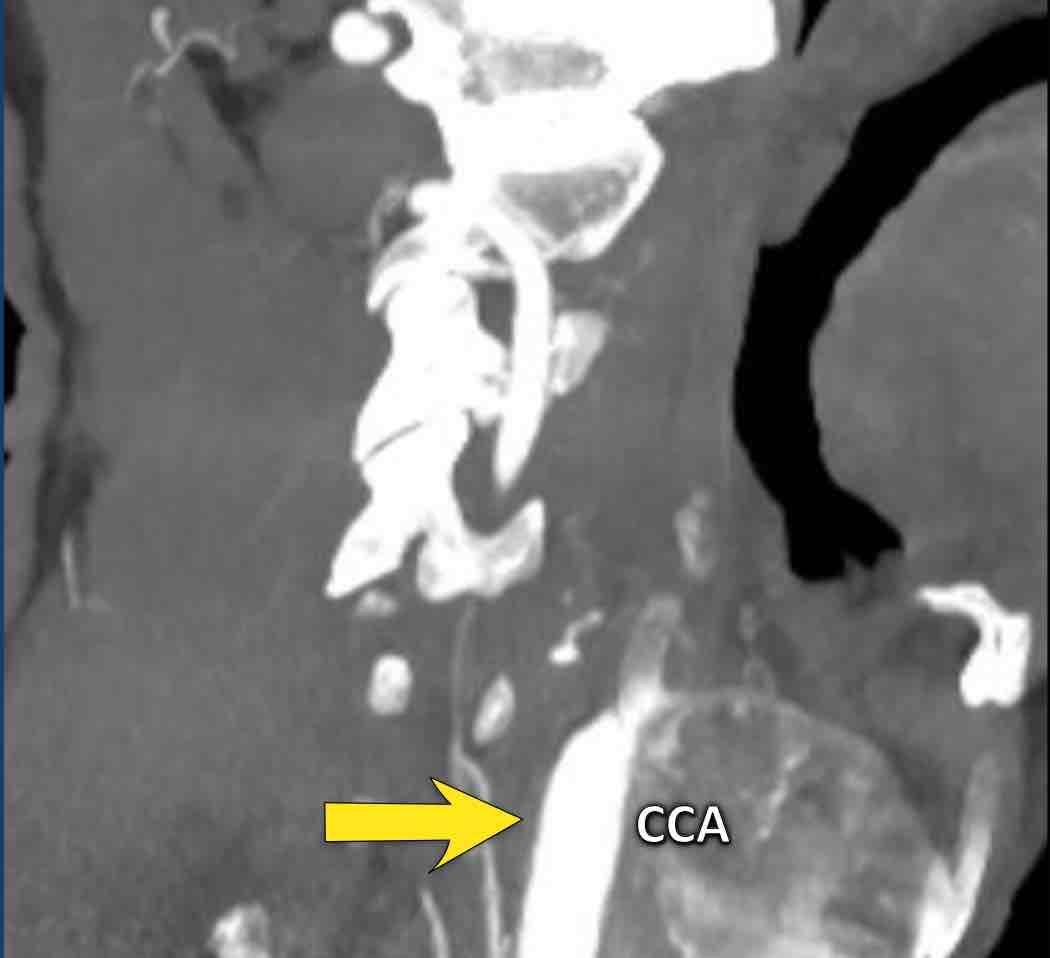

Gần tắc hoàn toàn (2)

Trong trường hợp này, động mạch cảnh chung có đường kính bình thường (hình 1).

Tiếp tục xem các ảnh mặt phẳng đứng dọc…

Bạn có thể cuộn qua các ảnh mặt phẳng đứng dọc.

Lưu ý mảng vôi hóa tại vị trí xoang cảnh và khẩu kính nhỏ của ICA đoạn xa, nhỏ hơn so với khẩu kính của ECA.